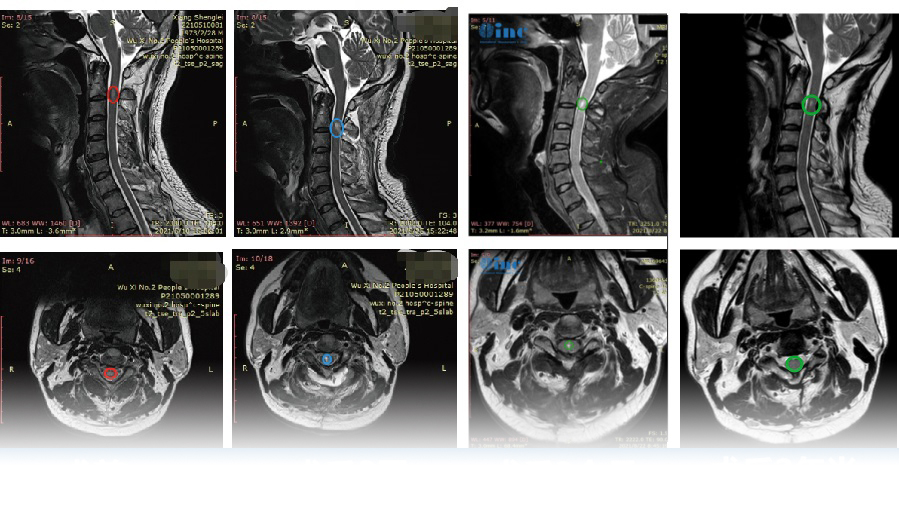

术前颈2平面脊髓内可见椭圆形短T1长T2信号,信号较均匀,边界尚清,大小约7.8X4.1X5.0mm,增强后明显强化。术后肿瘤得到顺利全切,无新发神经损伤,无瘫痪,术后复查没有复发

本来以为持续了半年多的脖子肩膀疼只是简单的颈椎病,万万没想到,一到医院核磁检查才发现是“脊髓内肿瘤”在作祟,颈2脊髓内可见明显病灶,大小约7.8X4.1X5.0mm。持续了3年左右的手抖且发麻可能也与此有关,也难怪他有时会头晕,平衡性不太好,闭目站不稳……

(患者术前病变)

刘先生的术前术后MRI对比